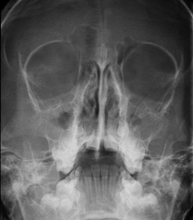

- Paranasal Sinuses X-ray

This technique uses X-ray rendered imaging for examining the paranasal sinuses. Indicated for: difficulty breathing through the nose, chronic cough, headache, mucus.

This technique uses X-ray rendered imaging for examining the paranasal sinuses. Indicated for: headache, chronic cough.